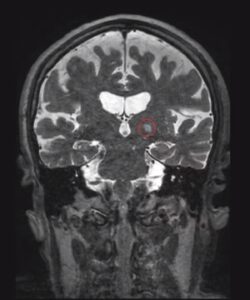

ومن الأمراض النادرة التي تثير اهتمامي بشكل خاص التشوهات الكهفية الدماغية[2] (Cerebral Cavernous Malformation – CCM). والتشوهات الكهفية الدماغية هي آفات في الدماغ تحدث عندما تنمو الخلايا المكونة للأوعية الدموية بشكل غير منضبط. وعلى الرغم من ندرتها، إلا أنها عندما تنمو وتنزف، يمكن أن تسبب أعراضًا عصبية منهكة.

ويُعد الاستئصال الجراحي لآفات الدماغ هو العلاج الأكثر شيوعًا للتشوهات الكهفية الدماغية؛ ومع ذلك، تقع بعض التشوهات الكهفية الدماغية في مناطق من الدماغ يصعب الوصول إليها، مما يزيد من خطر حدوث آثار جانبية. ويُعد الإشعاع خيارًا علاجيًا آخر، ولكنه أيضًا يمكن أن يؤدي إلى آثار جانبية خطيرة.

وقد وجدنا أن استخدام الموجات فوق الصوتية المركزة لفتح الحاجز الدموي الدماغي يمكن أن يُحسّن من توصيل الدواء إلى التشوهات الكهفية الدماغية. بالإضافة إلى ذلك، لاحظنا أيضًا أن العلاج بالموجات فوق الصوتية المركزة بحد ذاته يمكن أن يوقف نمو التشوهات الكهفية الدماغية لدى الفئران، حتى بدون إعطاء دواء.

وفي حين أننا لا نفهم بعد كيف تُسهم الموجات فوق الصوتية المركزة في استقرار التشوهات الكهفية الدماغية، إلا أن الأبحاث الوفيرة حول سلامة استخدام هذه التقنية لدى المرضى الذين يُعالجون من حالات أخرى سمحت لجراحي الأعصاب بالبدء في تصميم تجارب سريرية لاختبار استخدام هذه التقنية على الأشخاص المصابين بالتشوهات الكهفية الدماغية.